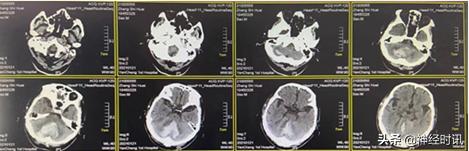

入院3 d后(1月21日),急诊头颅CT提示小脑内仍有大量血肿存在

1月26日(脑血疏用药5 d后)复查CT,患者小脑血肿开始逐渐淡化,血肿量明显减少,约20 ml,周围水肿并不明显,且环池变得清楚,继续服用脑血疏口服液